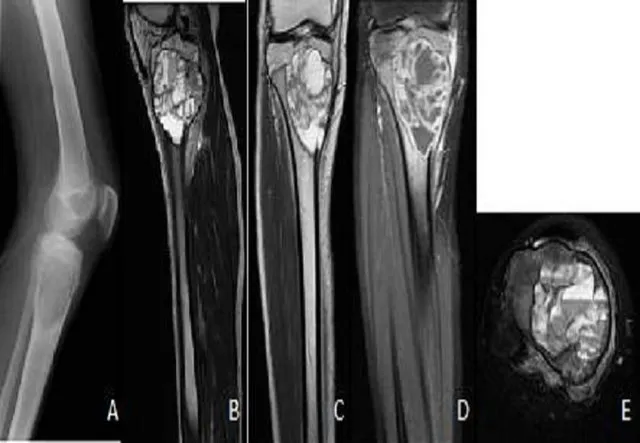

- Aneurysmal Bone Cyst (ABC)

- Benign, expansile, blood-filled cystic lesion; locally destructive.

- Age: 10-20 yrs; metaphysis (long bones), posterior spine.

- X-ray: "Soap bubble" appearance. MRI: Classic "fluid-fluid levels".

- Genetics: USP6 gene rearrangement (~70%).

- Tx: Curettage & bone grafting; sclerotherapy.

⭐ ABC is notorious for its "fluid-fluid levels" on MRI, a key diagnostic clue.